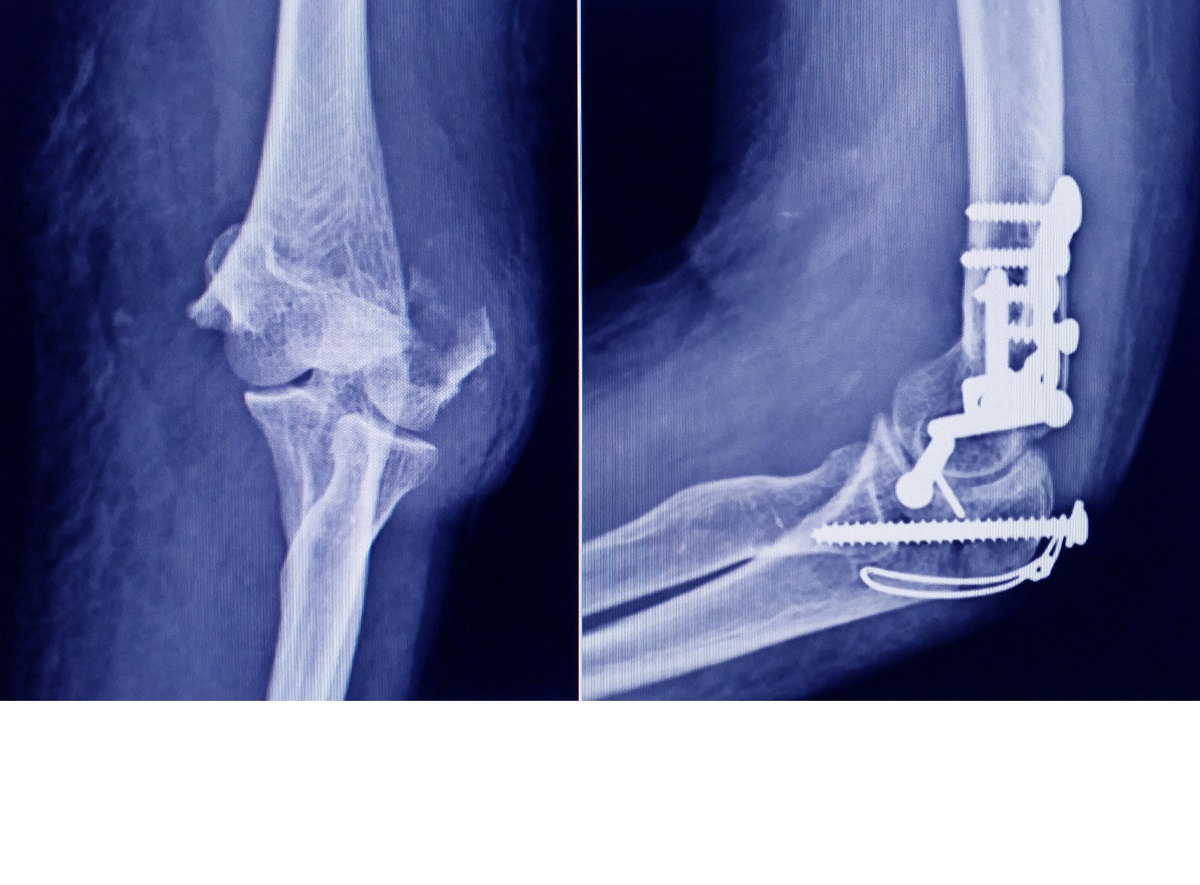

WebEl tiempo de recuperación de la osteosíntesis dependerá del manejo que se tomo y las características de la fractura. Como regla general una fractura consolida (pega) en. WebLa localización del dolor es un mal indicador del valor de la extracción del material de osteosíntesis. Tal vez habría que ofrecer la retirada a más pacientes. Esto. WebEn intervenciones quirúrgicas para la fijación de fracturas óseas se usan placas, clavos o tornillos para tratarlas. El uso de estos está indicado para mantener el.